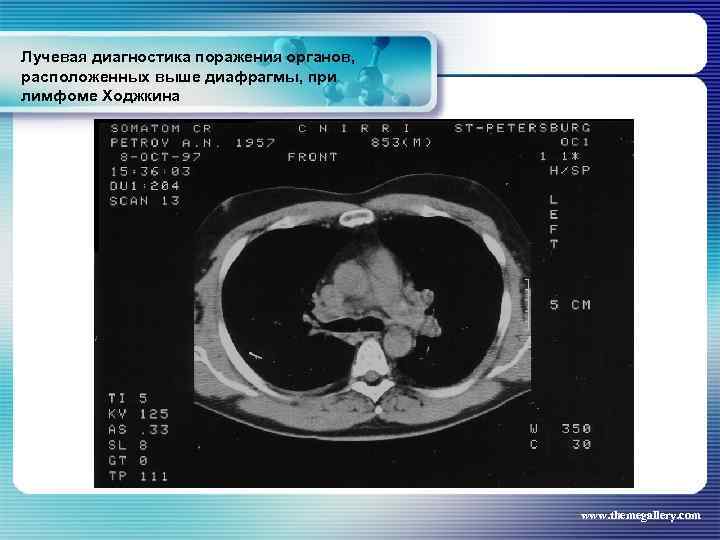

Лучевая диагностика поражения органов, расположенных выше диафрагмы, при лимфоме Ходжкина Частота поражения органов грудной полости при лимфоме Ходжкина: поражение средостения легких плевры грудной стенки - 66, 7 % 33, 75% 5, 3% 1, 8% www. themegallery. com

Лучевая диагностика поражения органов, расположенных выше диафрагмы, при лимфоме Ходжкина Частота поражения органов грудной полости при лимфоме Ходжкина: поражение средостения легких плевры грудной стенки - 66, 7 % 33, 75% 5, 3% 1, 8% www. themegallery. com

Лучевая диагностика поражения органов, расположенных выше диафрагмы, при лимфоме Ходжкина www. themegallery. com

Лучевая диагностика поражения органов, расположенных выше диафрагмы, при лимфоме Ходжкина www. themegallery. com

Лучевая диагностика поражения органов, расположенных выше диафрагмы, при лимфоме Ходжкина www. themegallery. com

Лучевая диагностика поражения органов, расположенных выше диафрагмы, при лимфоме Ходжкина www. themegallery. com

Лучевая диагностика поражения органов, расположенных выше диафрагмы, при лимфоме Ходжкина www. themegallery. com

Лучевая диагностика поражения органов, расположенных выше диафрагмы, при лимфоме Ходжкина www. themegallery. com

Лучевая диагностика поражения органов, расположенных выше диафрагмы, при лимфоме Ходжкина www. themegallery. com

Лучевая диагностика поражения органов, расположенных выше диафрагмы, при лимфоме Ходжкина www. themegallery. com

Лучевая диагностика поражения органов, расположенных выше диафрагмы, при лимфоме Ходжкина www. themegallery. com

Лучевая диагностика поражения органов, расположенных выше диафрагмы, при лимфоме Ходжкина www. themegallery. com

Лучевая диагностика поражения органов, расположенных выше диафрагмы, при лимфоме Ходжкина www. themegallery. com

Лучевая диагностика поражения органов, расположенных выше диафрагмы, при лимфоме Ходжкина www. themegallery. com

Лучевая диагностика поражения органов, расположенных выше диафрагмы, при лимфоме Ходжкина www. themegallery. com

Лучевая диагностика поражения органов, расположенных выше диафрагмы, при лимфоме Ходжкина www. themegallery. com

Лучевая диагностика поражения органов, расположенных выше диафрагмы, при лимфоме Ходжкина www. themegallery. com

Лучевая диагностика поражения органов, расположенных выше диафрагмы, при лимфоме Ходжкина www. themegallery. com

Лучевая диагностика поражения органов, расположенных выше диафрагмы, при лимфоме Ходжкина www. themegallery. com

Лучевая диагностика поражения органов, расположенных выше диафрагмы, при лимфоме Ходжкина www. themegallery. com

Лучевая диагностика поражения органов, расположенных выше диафрагмы, при лимфоме Ходжкина www. themegallery. com

Лучевая диагностика поражения органов, расположенных выше диафрагмы, при лимфоме Ходжкина www. themegallery. com

Лучевая диагностика поражения органов, расположенных выше диафрагмы, при лимфоме Ходжкина www. themegallery. com

Лучевая диагностика поражения органов, расположенных выше диафрагмы, при лимфоме Ходжкина www. themegallery. com

Лучевая диагностика поражения органов, расположенных выше диафрагмы, при лимфоме Ходжкина www. themegallery. com

Лучевая диагностика поражения органов, расположенных выше диафрагмы, при лимфоме Ходжкина www. themegallery. com